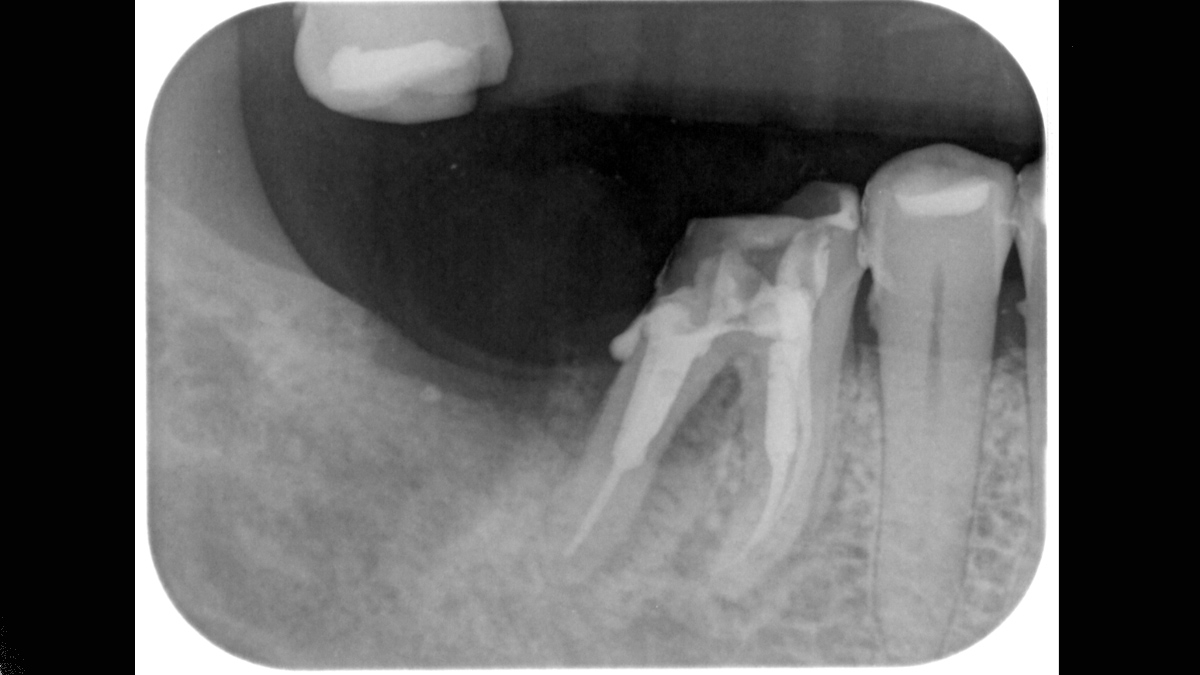

Xios Scan proporciona una introducción gentil y sencilla en el mundo de imágenes de rayos X digitales. Si desea cambiar de película a digital sin tener que renunciar a sus métodos de trabajo probados y reales, la tecnología de placa de imagen le ofrece un vistazo a las posibilidades. Puede experimentar muchas de las ventajas de la imagen digital sin salas oscuras y químicos mientras su equipo continúa con su flujo de trabajo normal.

Xios Scan se integra perfectamente con las unidades de rayos X de Dentsply Sirona y software para entregar diagnósticos intraorales más rápidos, seguros y mejores.